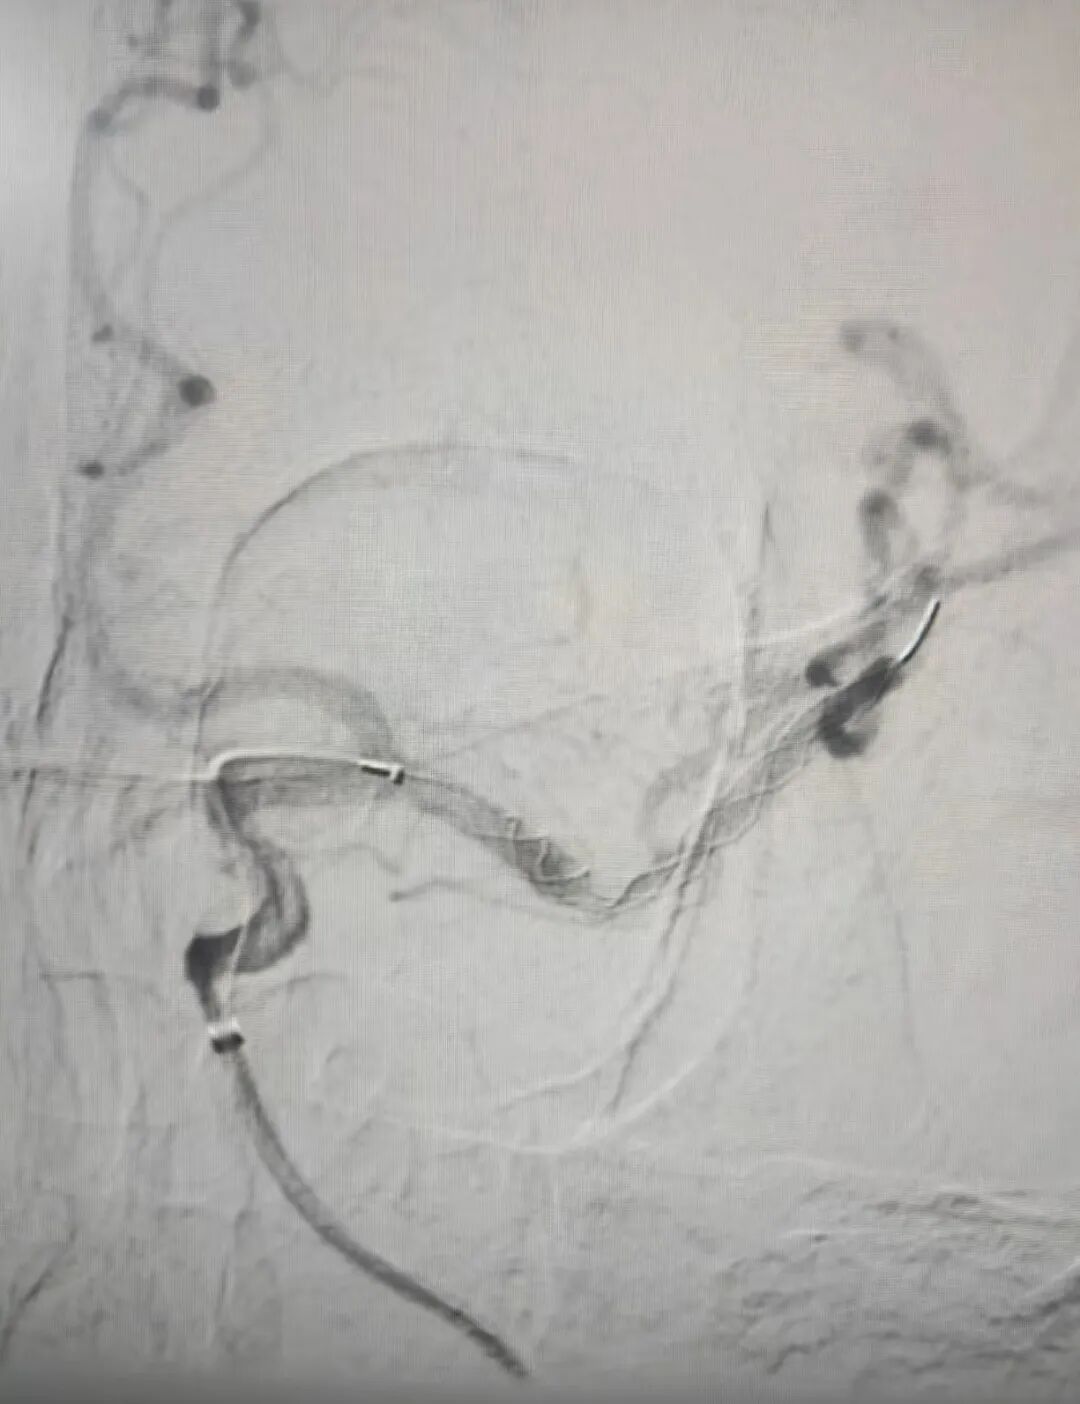

时间就是大脑!神经内科介入团队火速行动。19:50,患者被送入介入室,在局部麻醉下,邹永彪主任医师及其介入团队成员为患者立即施行了脑血管造影术,造影结果显示:左侧大脑中动脉闭塞,这是导致患者昏迷及右侧偏瘫的直接原因。团队凭借精湛技术,运用先进的取栓支架系统,精准定位并成功取出堵塞血管的暗红色血栓。术后造影显示,原先闭塞的左侧大脑中动脉及其分支恢复显影,前向血流重建!整个手术过程从穿刺到成功再通,仅用时约1小时。